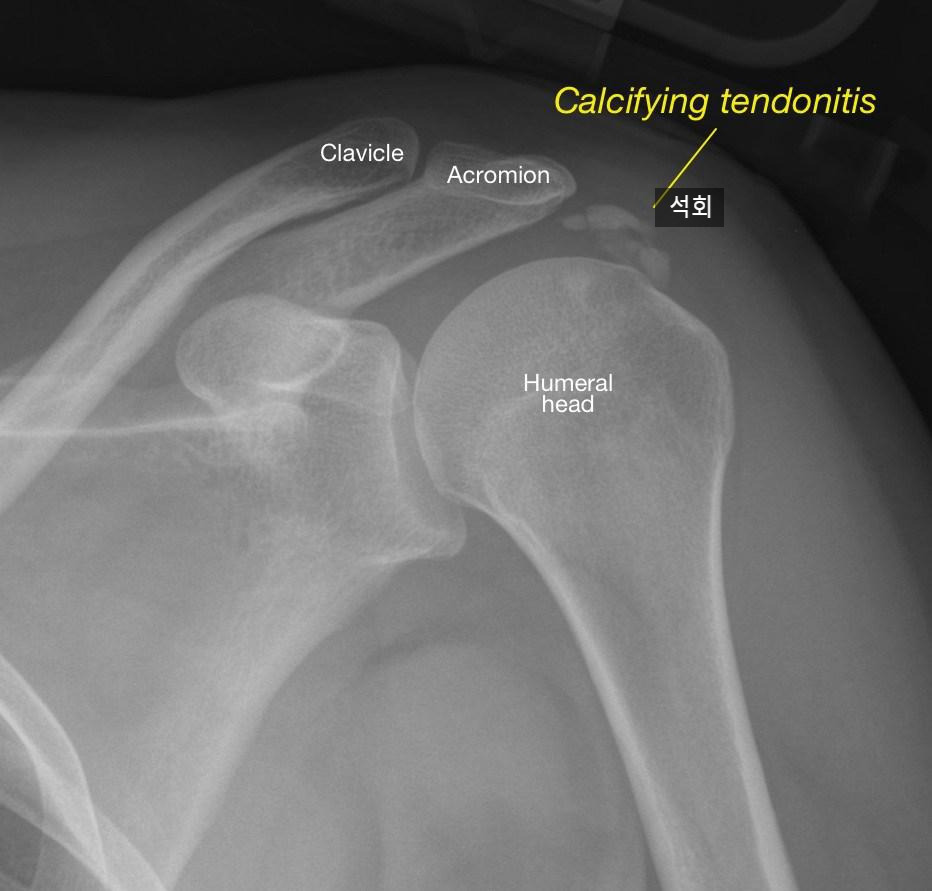

석회성건염은 어떻게 진단하나요?

특징적인 어깨 통증과 같은 증상과 엑스레이, 초음파 등으로 쉽게 확인할 수 있습니다.

엑스레이로 확인한 석회성건염